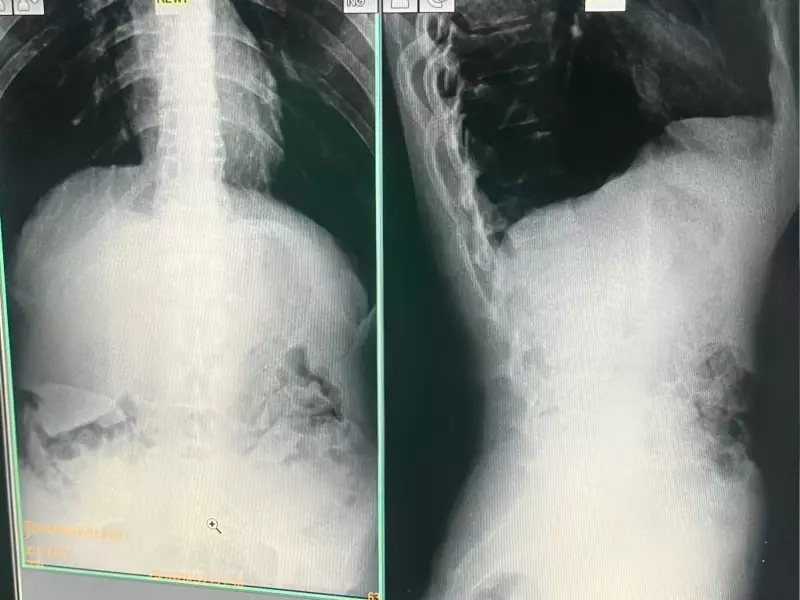

Ao desconfiarem do comportamento dos presos, os agentes penitenciários realizaram uma revista minuciosa que resultou na descoberta do plano. Os cinco indivíduos foram submetidos a exames que confirmaram a presença dos pacotes de drogas em seus organismos.